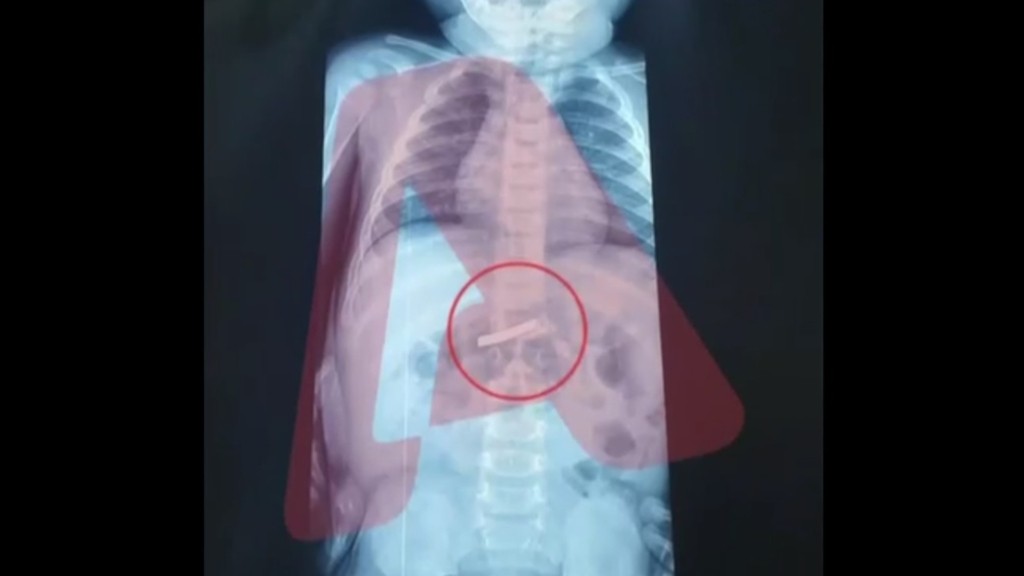

Σε κρίσιμη κατάσταση νοσηλεύονται στο νοσοκομείο Παπαγεωργίου της Θεσσαλονίκης οι δύο θεατές που τραυματίστηκαν στη διάρκεια αγώνα για το Πανελλήνιο Πρωτάθλημα Motocross, σε πίστα των Γιαννιτσών Πέλλας.

Οι δύο άτυχοι θεατές, ο ένας από τους οποίους ανήλικος, διακομίστηκαν αρχικά στο Νοσοκομείο Γιαννιτσών, αλλά οι γιατροί διαπίστωσαν ότι ήταν σοβαρά τραυματισμένοι και στη συνέχεια τους μετέφεραν στο Νοσοκομείο της Θεσσαλονίκης.

Σύμφωνα με πληροφορίες το ατύχημα σημειώθηκε όταν αναβάτης που συμμετείχε στους αγώνες, έχασε τον έλεγχο και η μοτοσικλέτα έπεσε πάνω σε προστατευτική περίφραξη και σε μεταλλική κολώνα με αποτέλεσμα να τραυματιστούν οι δύο άτυχοι θεατές.